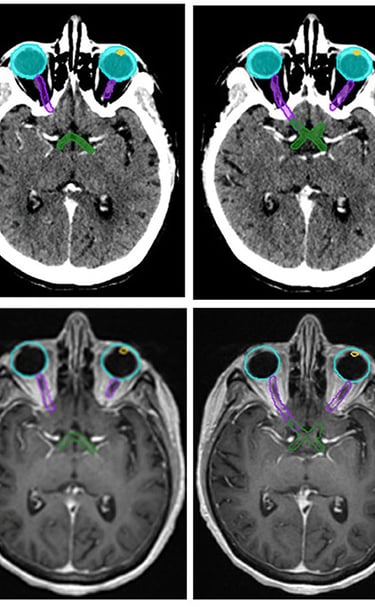

Gallery

Snapshots from patient journeys and expert insights